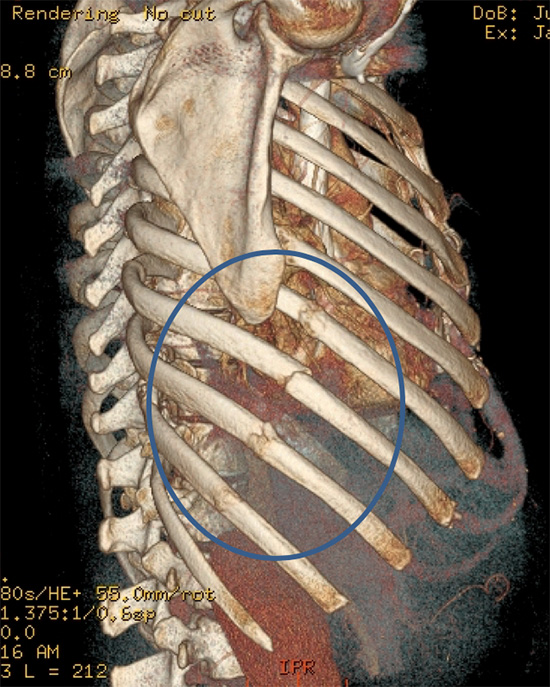

A broken rib typically causes sharp pain. To diagnose a rib injury, it’s best to see a medical professional who can look at your injuries with professional tools and technology. You may also feel or hear a crack or pop when the.

Sometimes, you may be able to feel a break in your rib by rubbing your finger over the rib. If you have a tender area on your ribs that hurts with every breath, you may have a broken rib. If you heard cracking during the injury or you hear or feel cracking when you move or.

Take slow, deep breaths and cough regularly to expand your lungs, use an incentive spirometer if asked to do so, get up and move around when you’re not sleeping,. When visiting your doctor, they will most likely be able to diagnose your injury simply by pushing on your chest and doing a physical exam. The pain you feel with a broken rib typically occurs or even worsens when you: